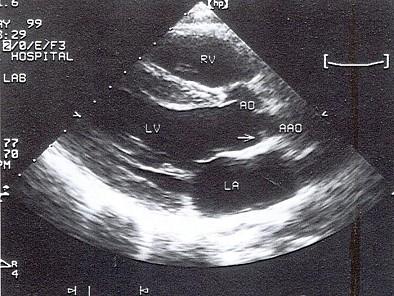

该病例最可能的诊断?(?)A.肥厚型心肌病B.高血压病C.左室流出道狭窄D.主动脉瓣下膜性狭窄E.主动脉瓣上狭窄

选项 A.肥厚型心肌病 B.高血压病 C.左室流出道狭窄 D.主动脉瓣下膜性狭窄 E.主动脉瓣上狭窄

答案 D